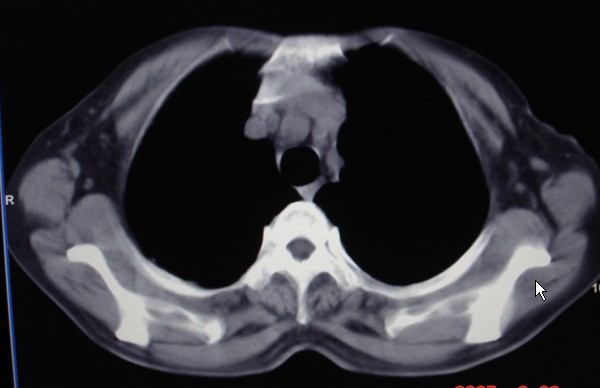

女,60岁咳嗽咳痰7天,痰中带血,有发热史,血象大约6000

双肺多发病灶,呈多形性,多叶分布,左上叶尖后段靠胸壁病灶伴有空洞,边缘模糊,与胸壁呈刀切征.

考虑混合感染以tb为主.

多灶,多形,少聚,少块。卫星灶,空洞影,树芽征,结核可能性大